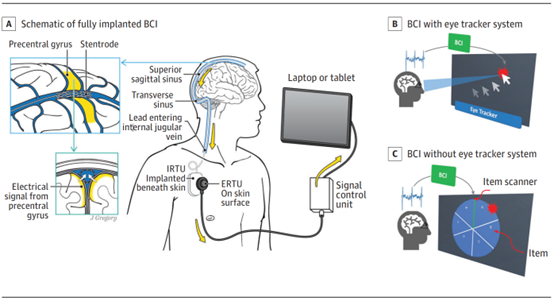

植入装置包括支架电极阵列,一种在血管内植入的16个电极传感装置,通过一根经血管的导线连接到锁骨下皮中的植入接收器发射器单元(IRTU)。传感装置的记录头包含表面积为0.3 mm2的铂电极,触点间距为3mm。数据以无线方式传输到外部控制器,该控制器将神经信号转换为开关输出,以控制计算机(图1A)。

图1.运动神经假体系统概述。A. 完全植入式的脑机接口(BCI)示意图。带有电极的设备被植入上矢状窦血管(插入),并连接到皮下的植入式接收发送单元(IRTU)。IRTU与外部接收器遥测单元(ERTU)通信,后者将信号中继到控制笔记本电脑或平板电脑的信号控制单元。B. BCI,眼动仪用于计算机控制。眼球跟踪用于移动光标,BCI用于点击。C. BCI无需眼动追踪,用于计算机控制。项扫描器按顺序高亮显示项,BCI用于在高亮显示项时单击项。